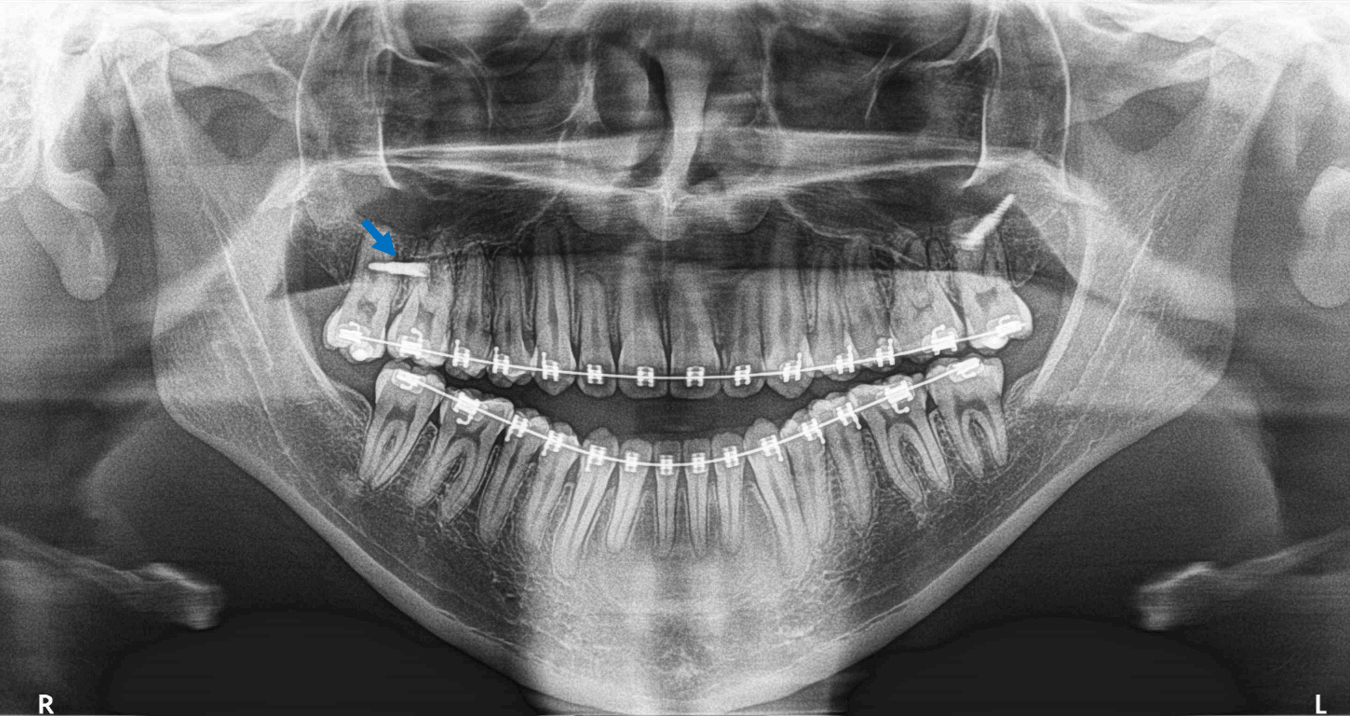

En la evaluación con tomografía volumétrica cone beam, en cortes transaxiales (Fig. 2) del órgano dentario 17 se observa una imagen hiperdensa (flecha azul) perforando la raíz palatina y condicionando la presencia de trazos de fractura (flechas rojas). La imagen hiperdensa se trata del dispositivo de fijación quirúrgica proyectado sobre el OD 17.